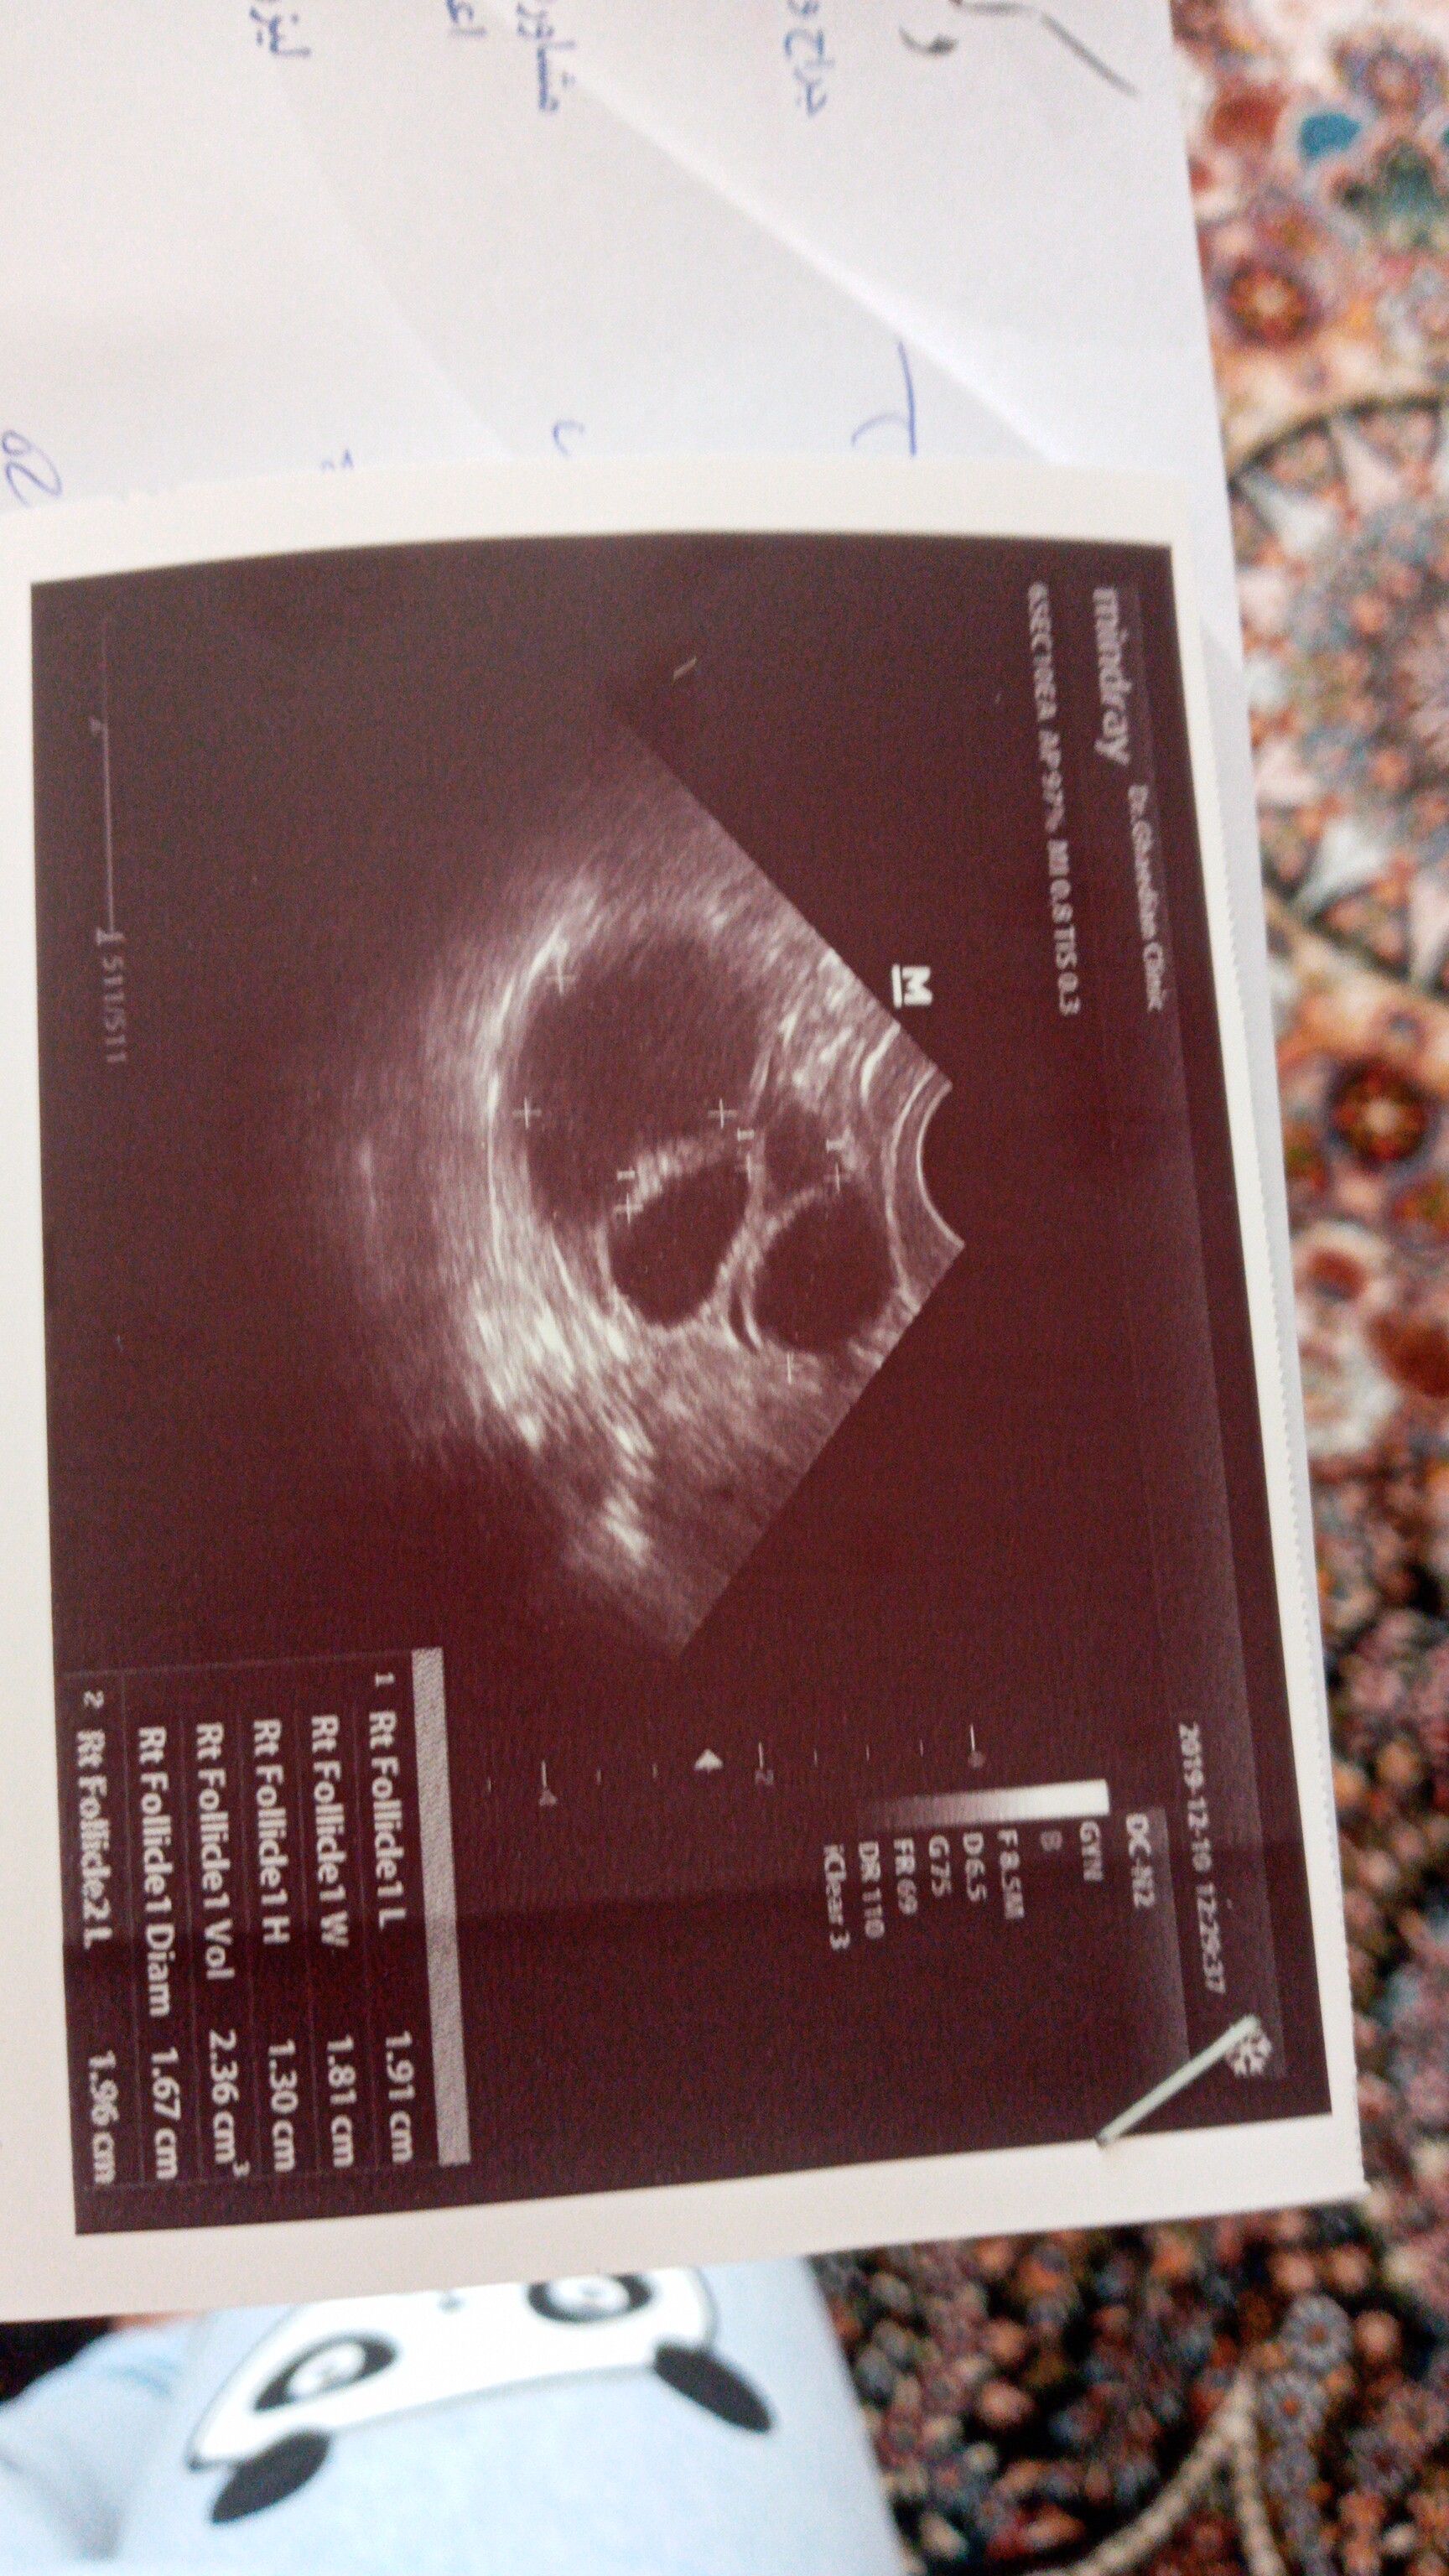

من سه شنبه ساعت ۷ امپول زدم.البته به گفته دکترم نصف امپولو زدم.ولی احساس میکنم باید همشو میزدم تا تخمکم ازاد بشه.الان عکس سونو رو میزارم

چون دکترم گفت تخمکات بزرگه نصفشو بزن🥺🥺

اینا چیه تو رحمت😐

تخمک😐

چند بود

به این بزرگی😲

۱۸-۱۹-۲۰-۲۱ بودن روز ۱۳ پری بود